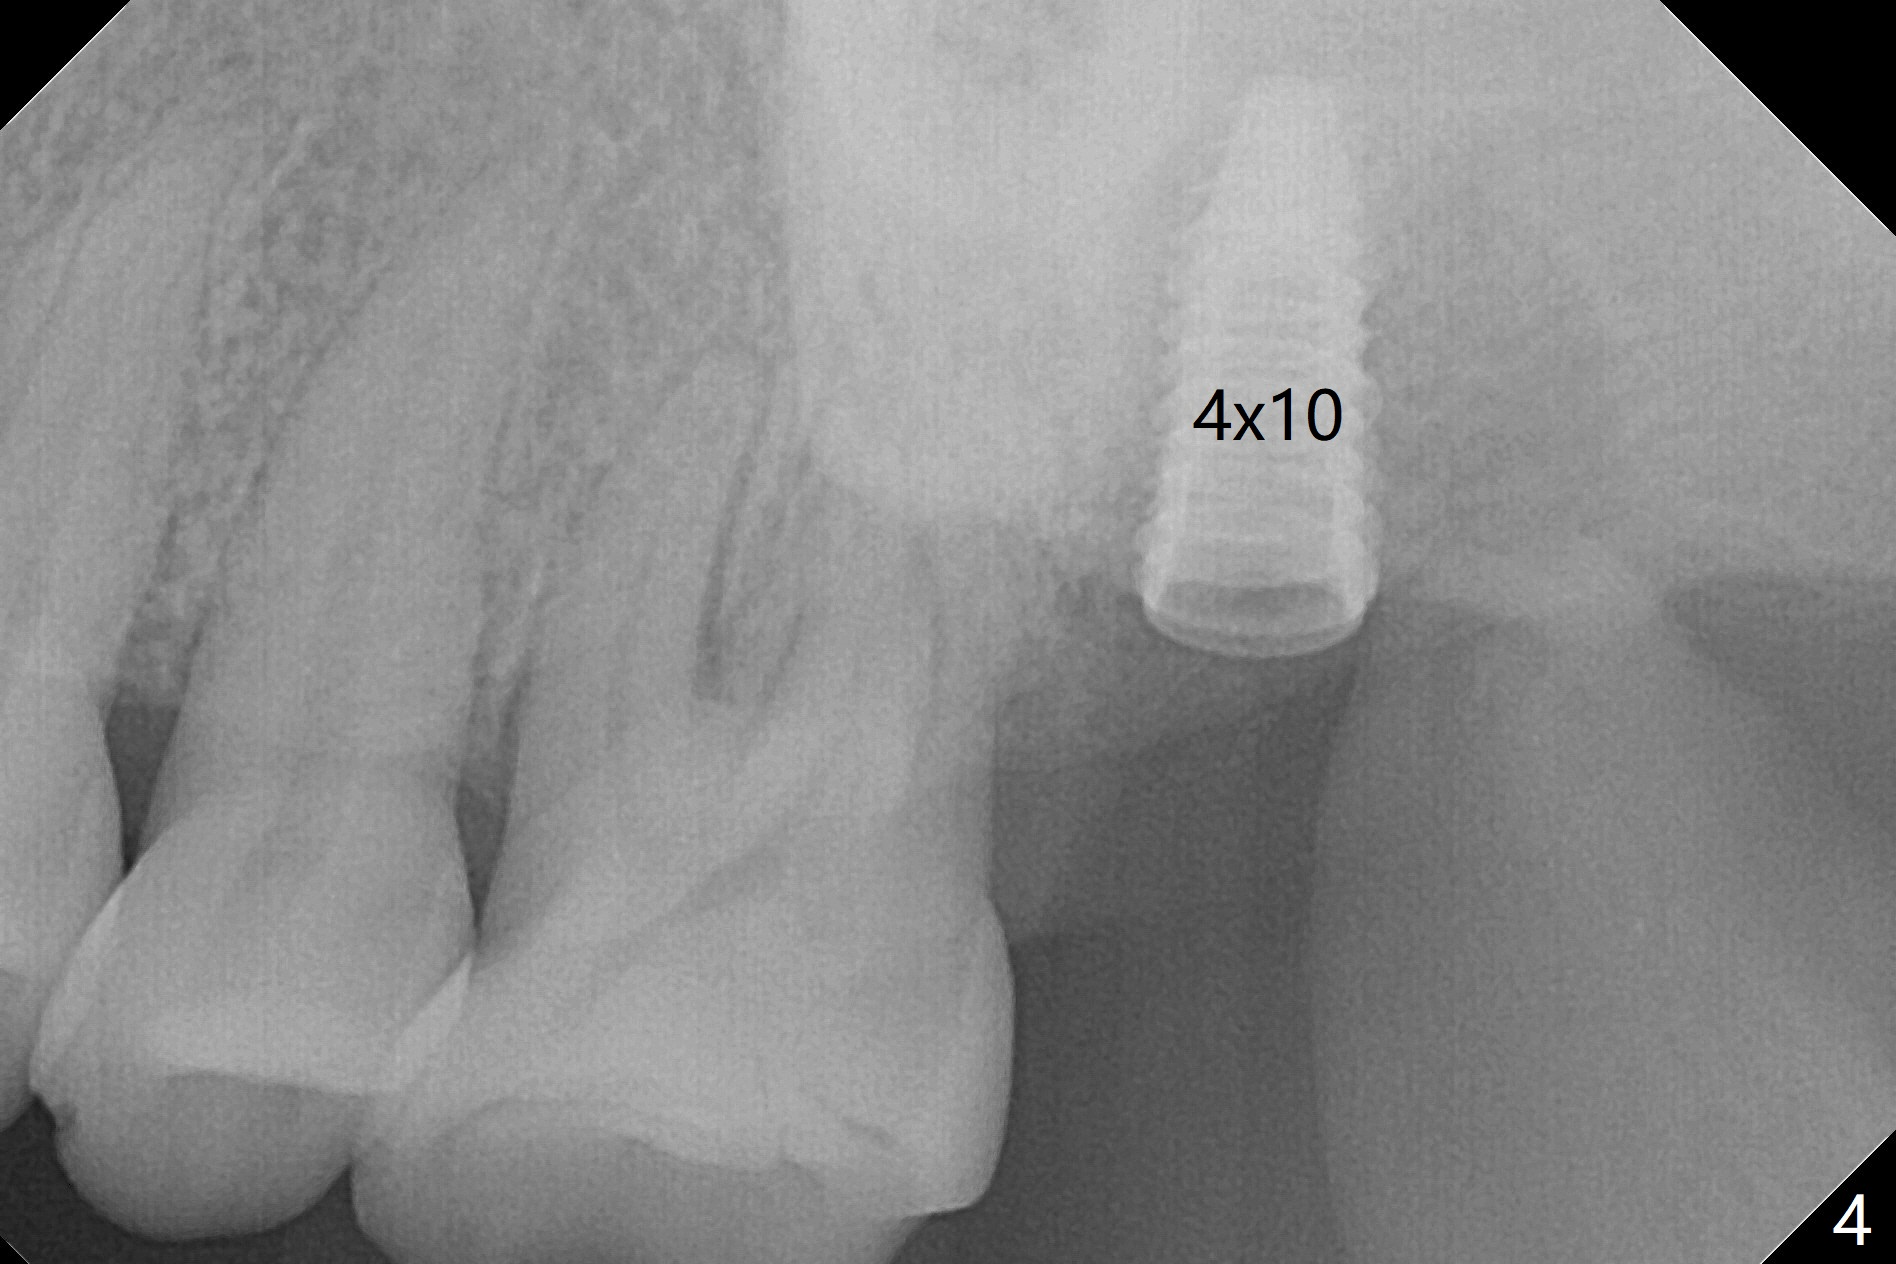

Although the buccal (Fig.1 (mesial view of the extracted tooth #15): B) root is larger than the palatal (P) one, the palatal socket is larger than the buccal one (Fig.2 white area) because of the bone loss of the former. For better restoration, osteotomy (Fig.2 red line) is initiated in the buccal slope of the septum (S) so that the final osteotomy is in the middle of the whole socket (Fig.3 red box). In fact a 3 mm stopper is not used because of the slope and the clumsy stopper. Stopper would be indicated if the bottom of the bone were flat. At first a 4x10 mm dummy implant is placed with stability (Fig.4). After further osteotomy and sinus lift (Fig.6 red dashed line: sinus floor), a 5x10 mm implant is placed with 30 Ncm, followed by insertion of a 5.2x8(2) mm temporary abutment (Fig.5,6). The latter holds an immediate provisional and Vanilla Graft/Osteogen (Fig.7 *) in place (^: distal crestal bone). Although the bone looks normal around the implant 7.5 months postop (Fig.4), the implant is unstable, probably due to the large preexisting defect. In contrast the implant placed at the healed site of #3 is stable 6.5 months postop. The 8x5 mm healing abutment that dislodged for 1 day could not return. A 6x5 mm one is used; it appears that the bone density mesial and distal to the implant is low (Fig.9 *). The implant looks normal and is stable 13 months postop (Fig.10). A 5.7x5.5(5) mm cementation abutment is placed for a provisional (progressive loading, Fig.11). There is no pain associated with the provisional for mastication. Impression is taken 7 days later. The patient has pain when the permanent crown is cemented. It appears that the implant does not osteointegrate and should be removed. A 6x14 mm tissue-level implant will be immediately placed following a 5 and 6x14 mm taps and bone graft and PRF (Metronidazole). In fact there is no pain when the existing abutment is torqued at 35 Ncm 1 year 8 months postop (Fig.12). The mesiogingival portion of final restoration (Fig.13 arrowheads) should be bulky so that the gingival embrasure (red dashed line) is minimal to reduce food impaction.